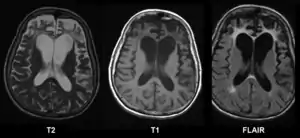

При гістологічному дослідженні тканини головного мозку в нейронах знаходяться незвичайні включення. Пірамідні нейрони набрякають, містять цитоплазматичні тільця Піка. Товщина сірої речовини зменшена, межа між сірою і білою речовиною розмита. Зазначається розширення шлуночків (переважно передніх рогів бічних шлуночків) і субарахноїдального простору, поглиблення борозен півкуль.